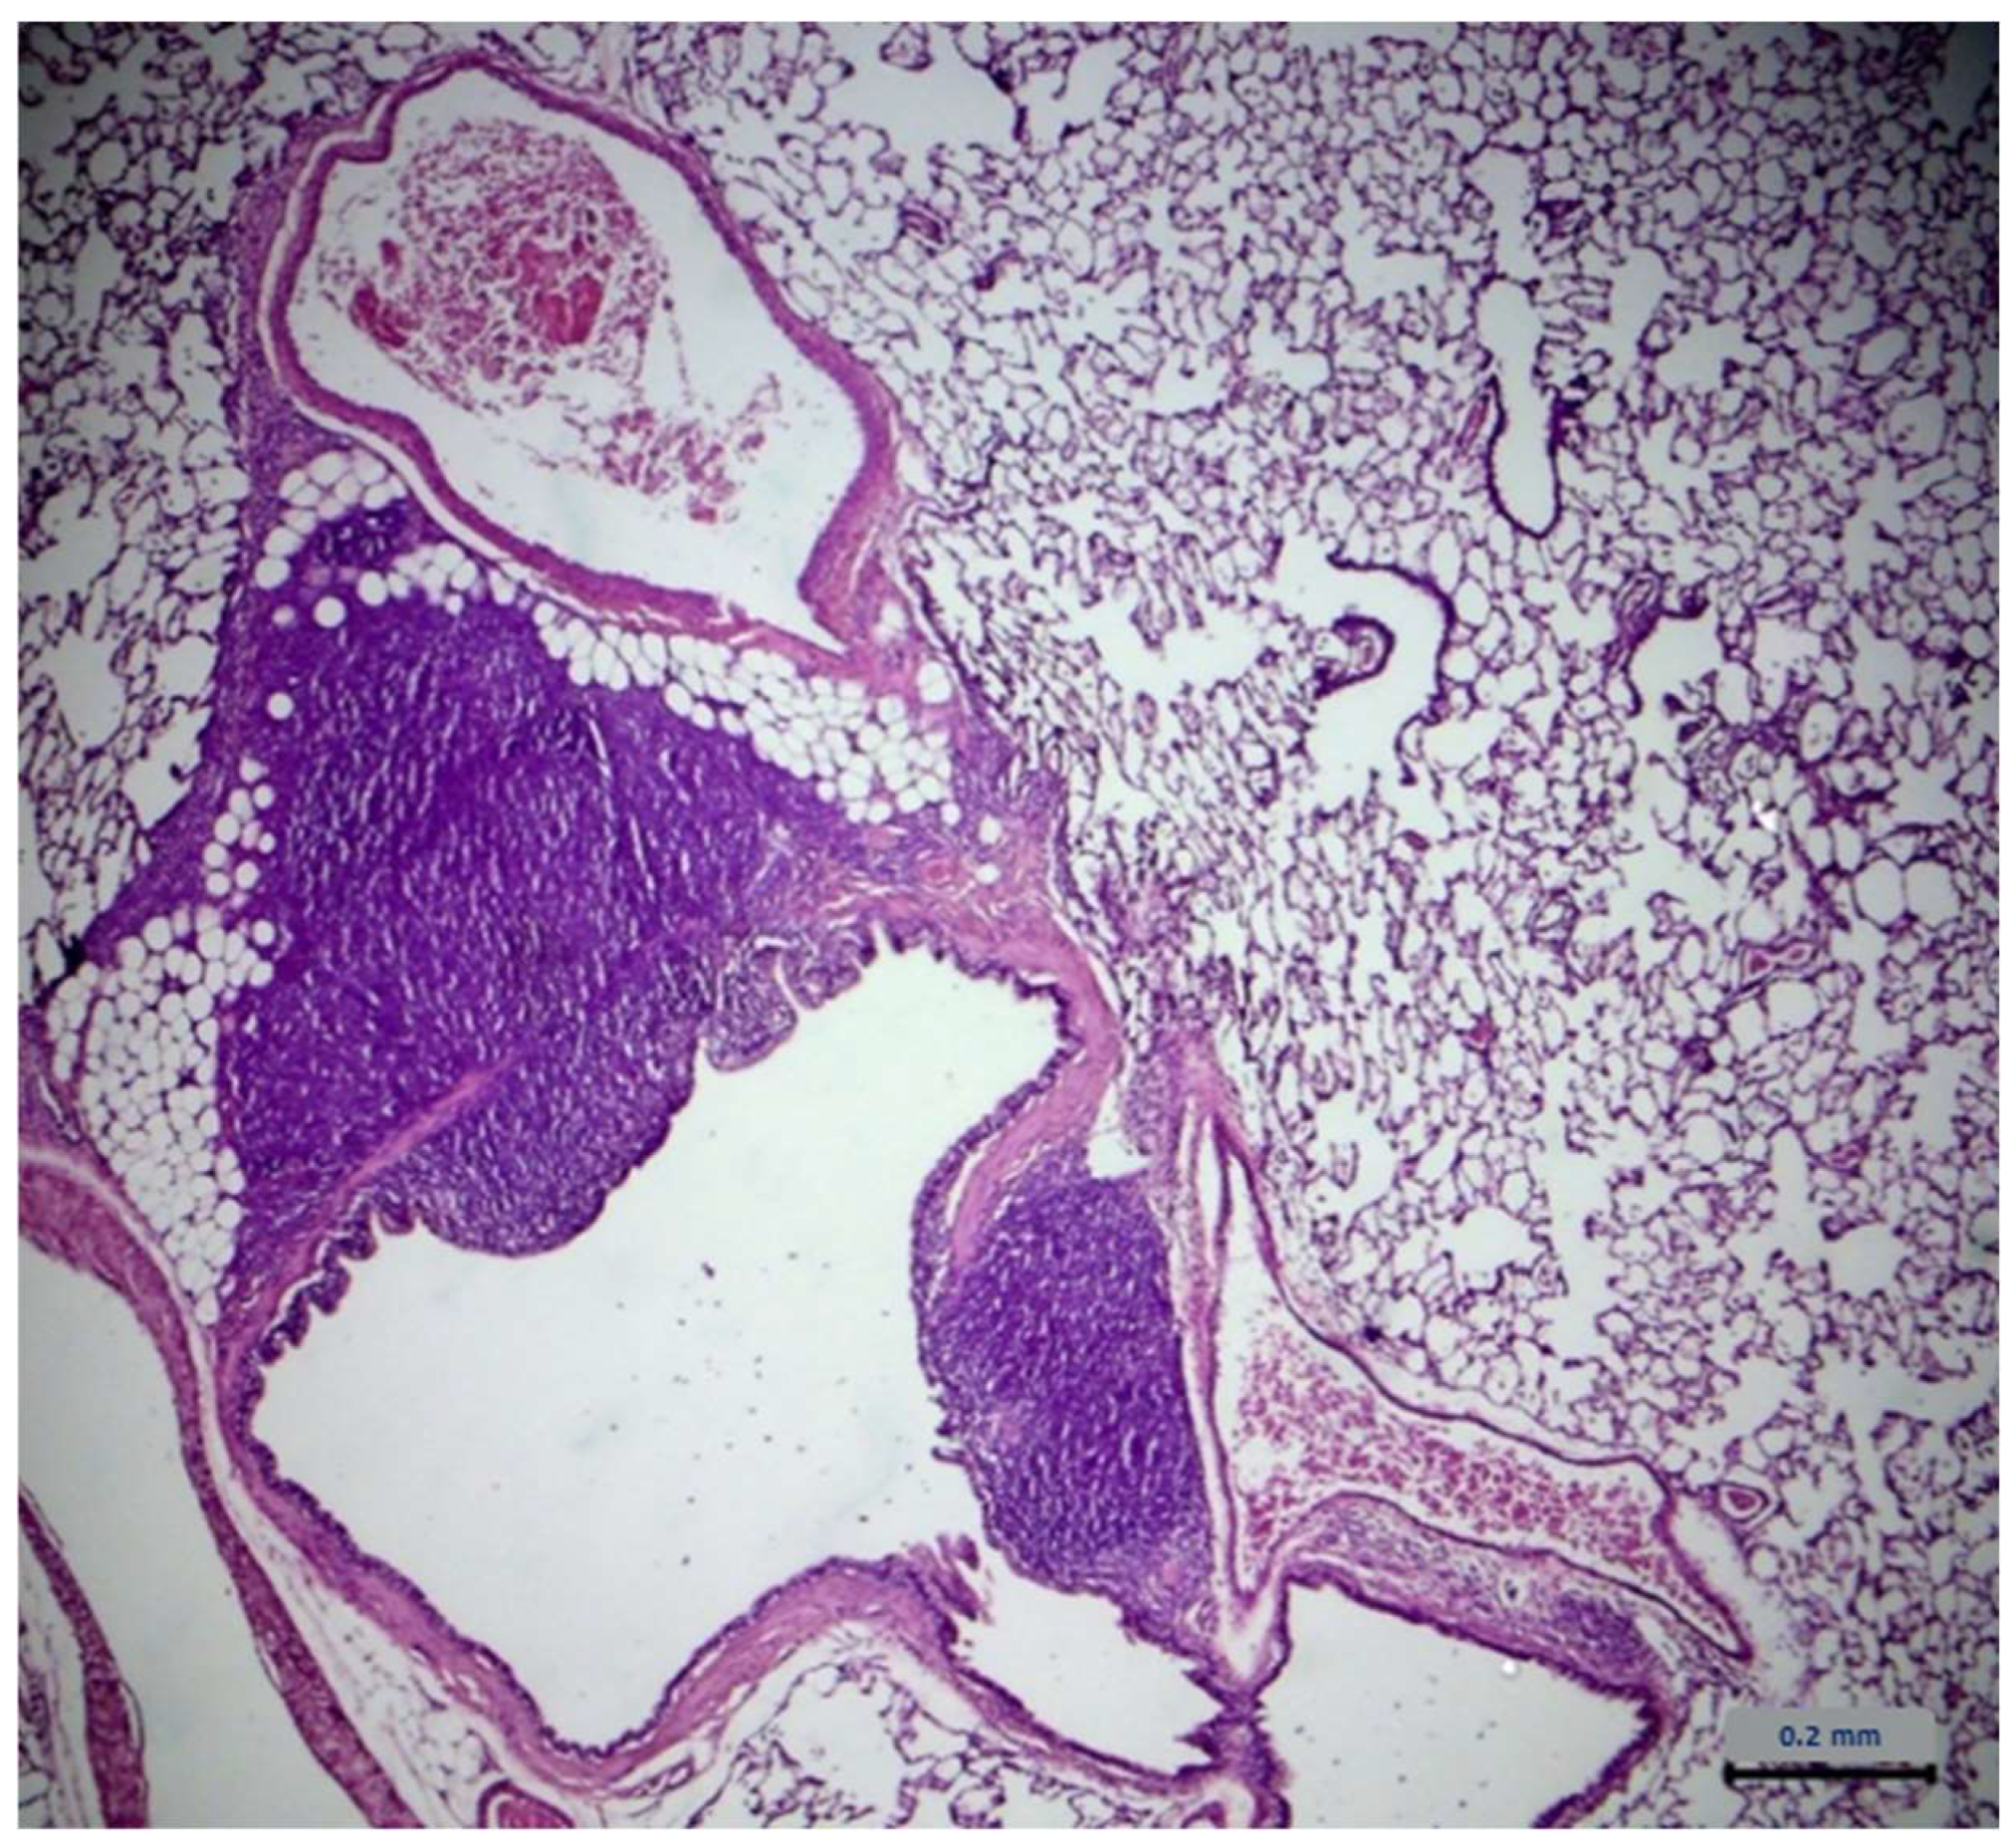

2.7. Histopathological Assessment

- Albers, T.M.; Simon, M.A.; Clifford, C.B. Histopathology of Naturally Transmitted “Rat Respiratory Virus”: Progression of Lesions and Proposed Diagnostic Criteria. Vet. Pathol. 2009, 46, 992–999. [Google Scholar] [CrossRef]

- Slaoui, M.; Dreef, H.C.; Van Esch, E. Inflammatory Lesions in the Lungs of Wistar Rats. Toxicol. Pathol. 1998, 26, 712–713, discussion 714. [Google Scholar] [CrossRef] [PubMed]

- Elwell, M.R.; Mahler, J.F.; Rao, G. “Have You Seen This?” Inflammatory Lesions in the Lungs of Rats. Toxicol. Pathol. 1997, 25, 529–531. [Google Scholar] [CrossRef]

| Lung Type of Lesions | Control Group n = 6 | Extract Group n = 6 |

|---|---|---|

| Architecture | - 1 | - |

| Cell degeneration/necrosis | - | - |

| Inflammatory filtration | 4 2 | 4 |

| Hemodynamic damage | - | - |

| Cell growth disorders | - | - |

| Lung Severity | Control Group n = 4 | Extract Group n = 4 |

| Minimum | - | - |

| Mild | 3 1 | 2 |

| Medium | 1 2 | 2 |

| Serious | - | - |